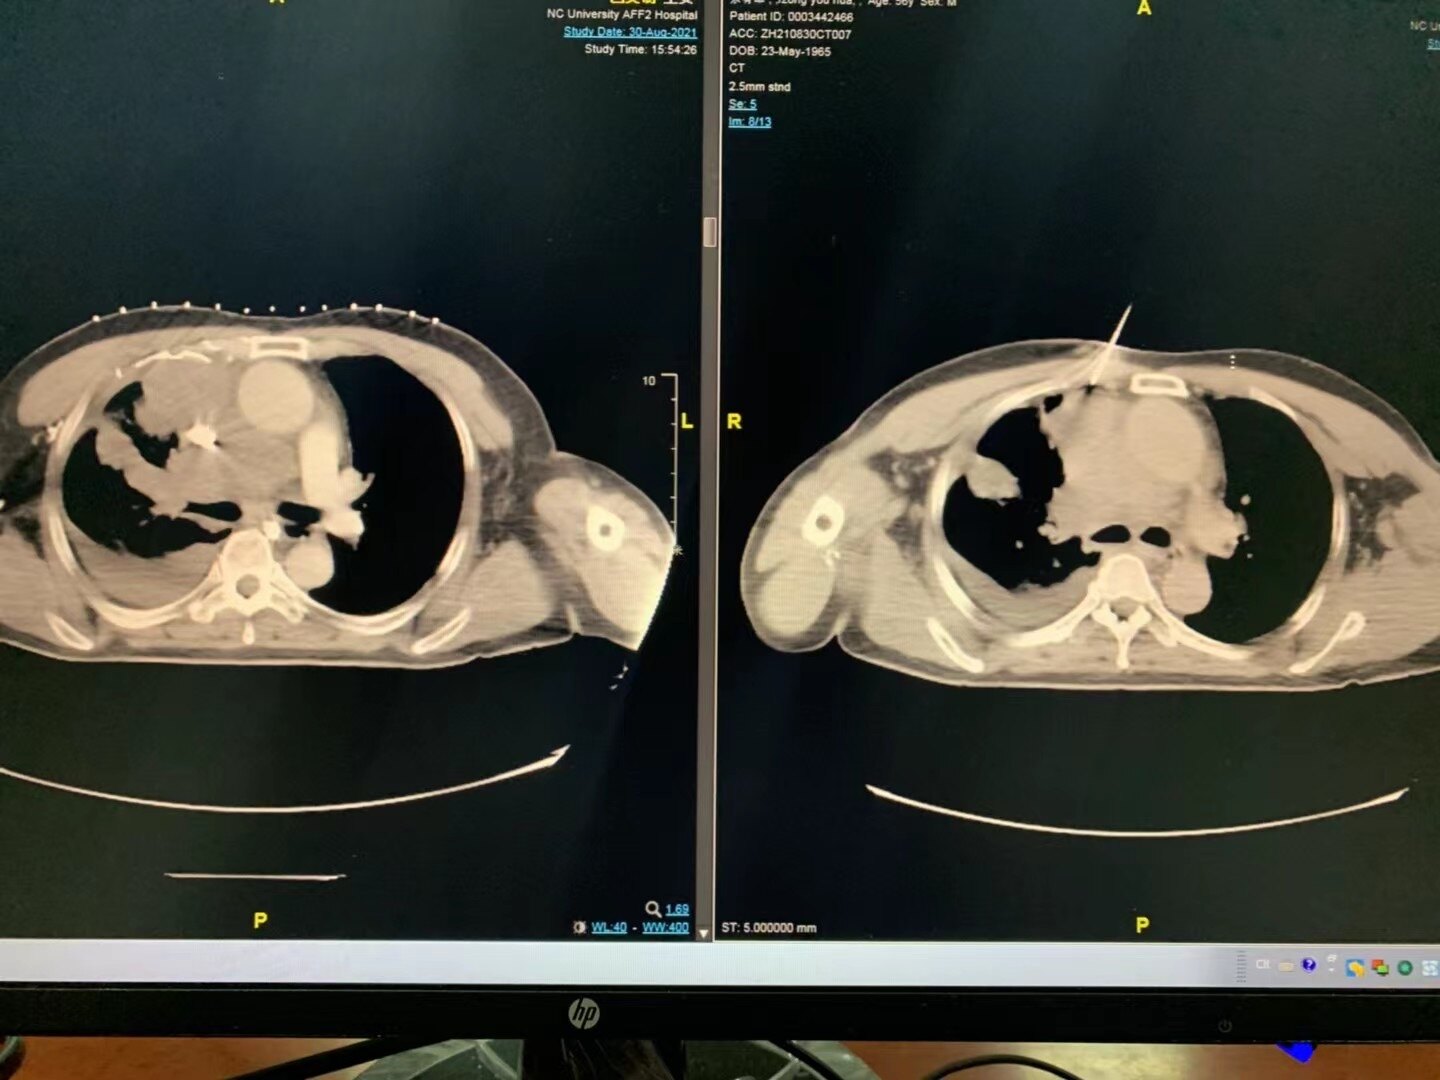

为明确诊断,给予ct引导下的右肺占位穿刺活检术.

图片尺寸2667x2000

ct引导下肺肿瘤活检